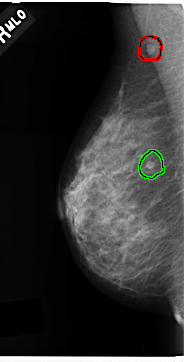

FILE: C_0212_1.RIGHT_MLO.OVERLAY

TOTAL_ABNORMALITIES 2

ABNORMALITY 1

LESION_TYPE MASS SHAPE ROUND MARGINS CIRCUMSCRIBED

ASSESSMENT 4

SUBTLETY 5

PATHOLOGY MALIGNANT

TOTAL_OUTLINES 1

BOUNDARY

ABNORMALITY 2